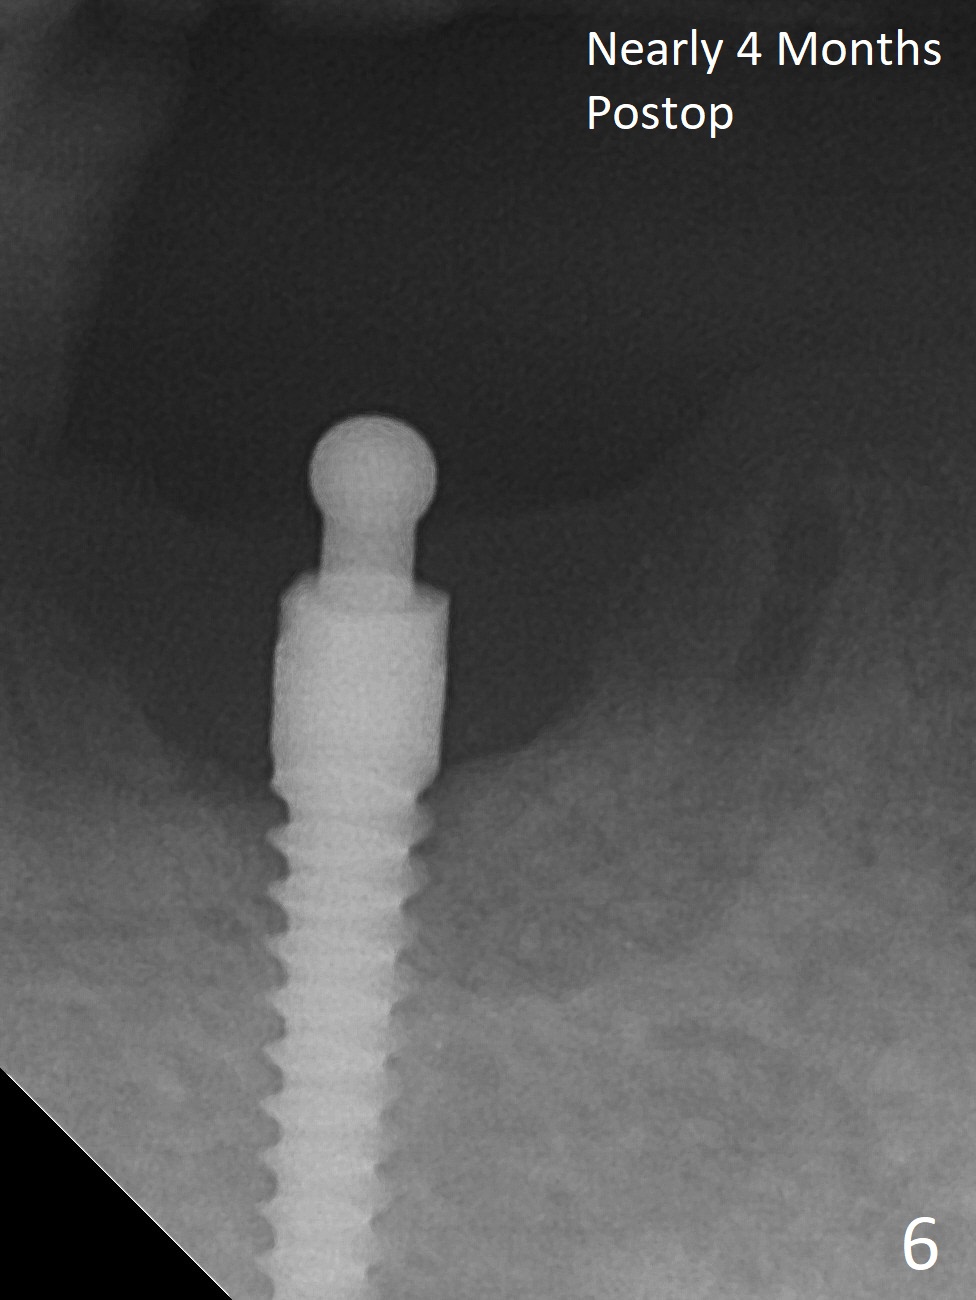

The ridge at #27 is narrow and is reduced ~ 4 mm in height (Fig.1 *) to obtain ~ 4 mm buccolingual width. A 3x14 mm 1-piece implant with ball abutment is placed (Fig.3 (*: bone graft)). In contrast, there is no problem of the buccolingual width after #22 extraction; initial osteotomy depth is 14 mm to gain ~ 5 mm of the native bone for primary stability (Fig.2). Since the lingual crest is significantly lower than the buccal one, a shorter implant (2-piece, 3.8x12 mm, Fig.4) is placed so that a ball abutment with a longer cuff is chosen (4 mm). Soft reline is applied to the site of #22 with minimal retention. But the patient is pleased with the "pain-free" procedure. It appears that gingivectomy is required for the ball abutments in 2 months (Fig.5). The implants seem osteotointegrated nearly 4 months postop (Fig.6,7). Ten months postop, the patient will return for fabrication of new full dentures to correct Class II relationship. There is mild or no bone loss 2 year 4 months postop (Fig.8,9), although the housing at #27 is dislodged. Return to Lower Canine Immediate Implant, Armaments Overdentures Xin Wei, DDS, PhD, MS 1st edition 07/24/2018, last revision 12/18/2020